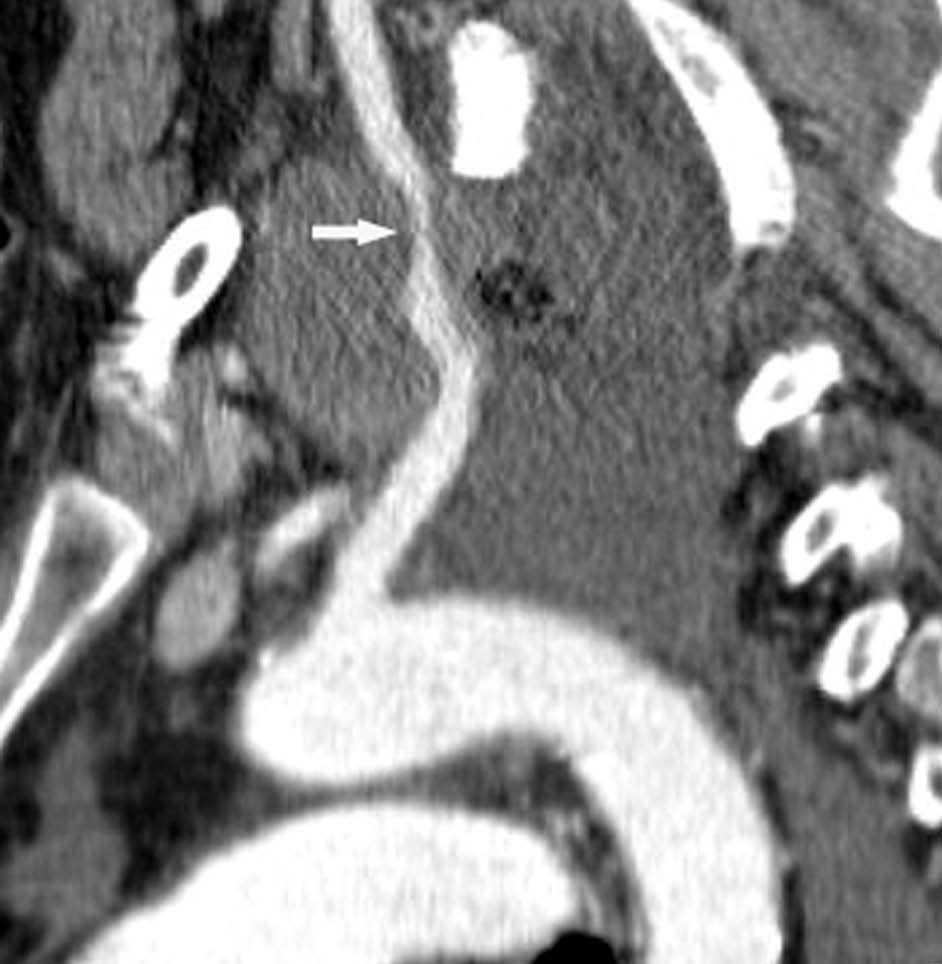

Valoración del tumor

El estadio tumoral (T) se basa en el tamaño, localización y relación con las estructuras adyacentes valorado mediante TC. Los tumores T1 son aquellos de 3 cm o menores en su diámetro mayor, rodeados de pulmón y que no invaden la pleura visceral ni los bronquios principales, mientras que los T2 son lesiones mayores de 3 cm, o aquellas que invaden la pleura visceral o al bronquio principal a más de 2 cm de la carina o que condicionan atelectasia o neumonitis obstructiva que no afecte a todo el pulmón. La diferenciación entre ambos estadios tumorales suele ser sencilla mediante TC, salvo la afectación de la pleura visceral, aunque esta no tiene un impacto importante en el manejo clínico. El tumor T3 viene determinado por la infiltración de estructuras vecinas potencialmente resecables, como la pared torácica, diafragma, pleura mediastínica, pericardio parietal o si el tumor está situado a menos de 2 cm de la carina (fig. 1). Los tumores T4 son aquellos que no pueden ser resecados porque engloban a estructuras vitales, invaden el corazón, grandes vasos, esófago o cuerpos vertebrales (fig. 2) o en los que existe un nódulo o nódulos en el mismo lóbulo del tumor. Además de definir la T, es importante reflejar las particularidades de la infiltración de estructuras en vecindad que puedan modificar la actitud terapéutica. Por ejemplo, cambiará la estrategia quirúrgica según el tipo de bronquio afecto o la estructura mediastínica infiltrada, si es sólo la grasa, o un vaso; cuando existe neumonitis o atelectasia secundaria a un tumor central, la planificación del campo de radioterapia dependerá del límite entre la masa y la repercusión pulmonar.

La diferenciación entre tumores T3 y T4 puede ser difícil empleando sólo técnicas de imagen. Cuando se evidencia destrucción ósea (costal o vertebral), existe masa en el espacio intercostal (fig. 3), o las estructuras mediastínicas están claramente englobadas por el tumor, el diagnóstico es obvio (fig. 2). Sin embargo, sin estos hallazgos, la predicción de invasión es mucho menos fiable. Se han descrito diferentes signos que pueden ayudar a determinar la invasión de pared torácica. Éstos incluyen el contacto con la superficie pleural mayor de 3 cm, el engrosamiento pleural, la ausencia de plano graso y la presencia de un ángulo obtuso entre el tumor y la pared torácica. Aplicando al menos dos de estos criterios la sensibilidad es de un 87%, sin embargo la especificidad es baja (59%)4. El dolor torácico localizado es un síntoma importante que a menudo está asociado a invasión de pared.